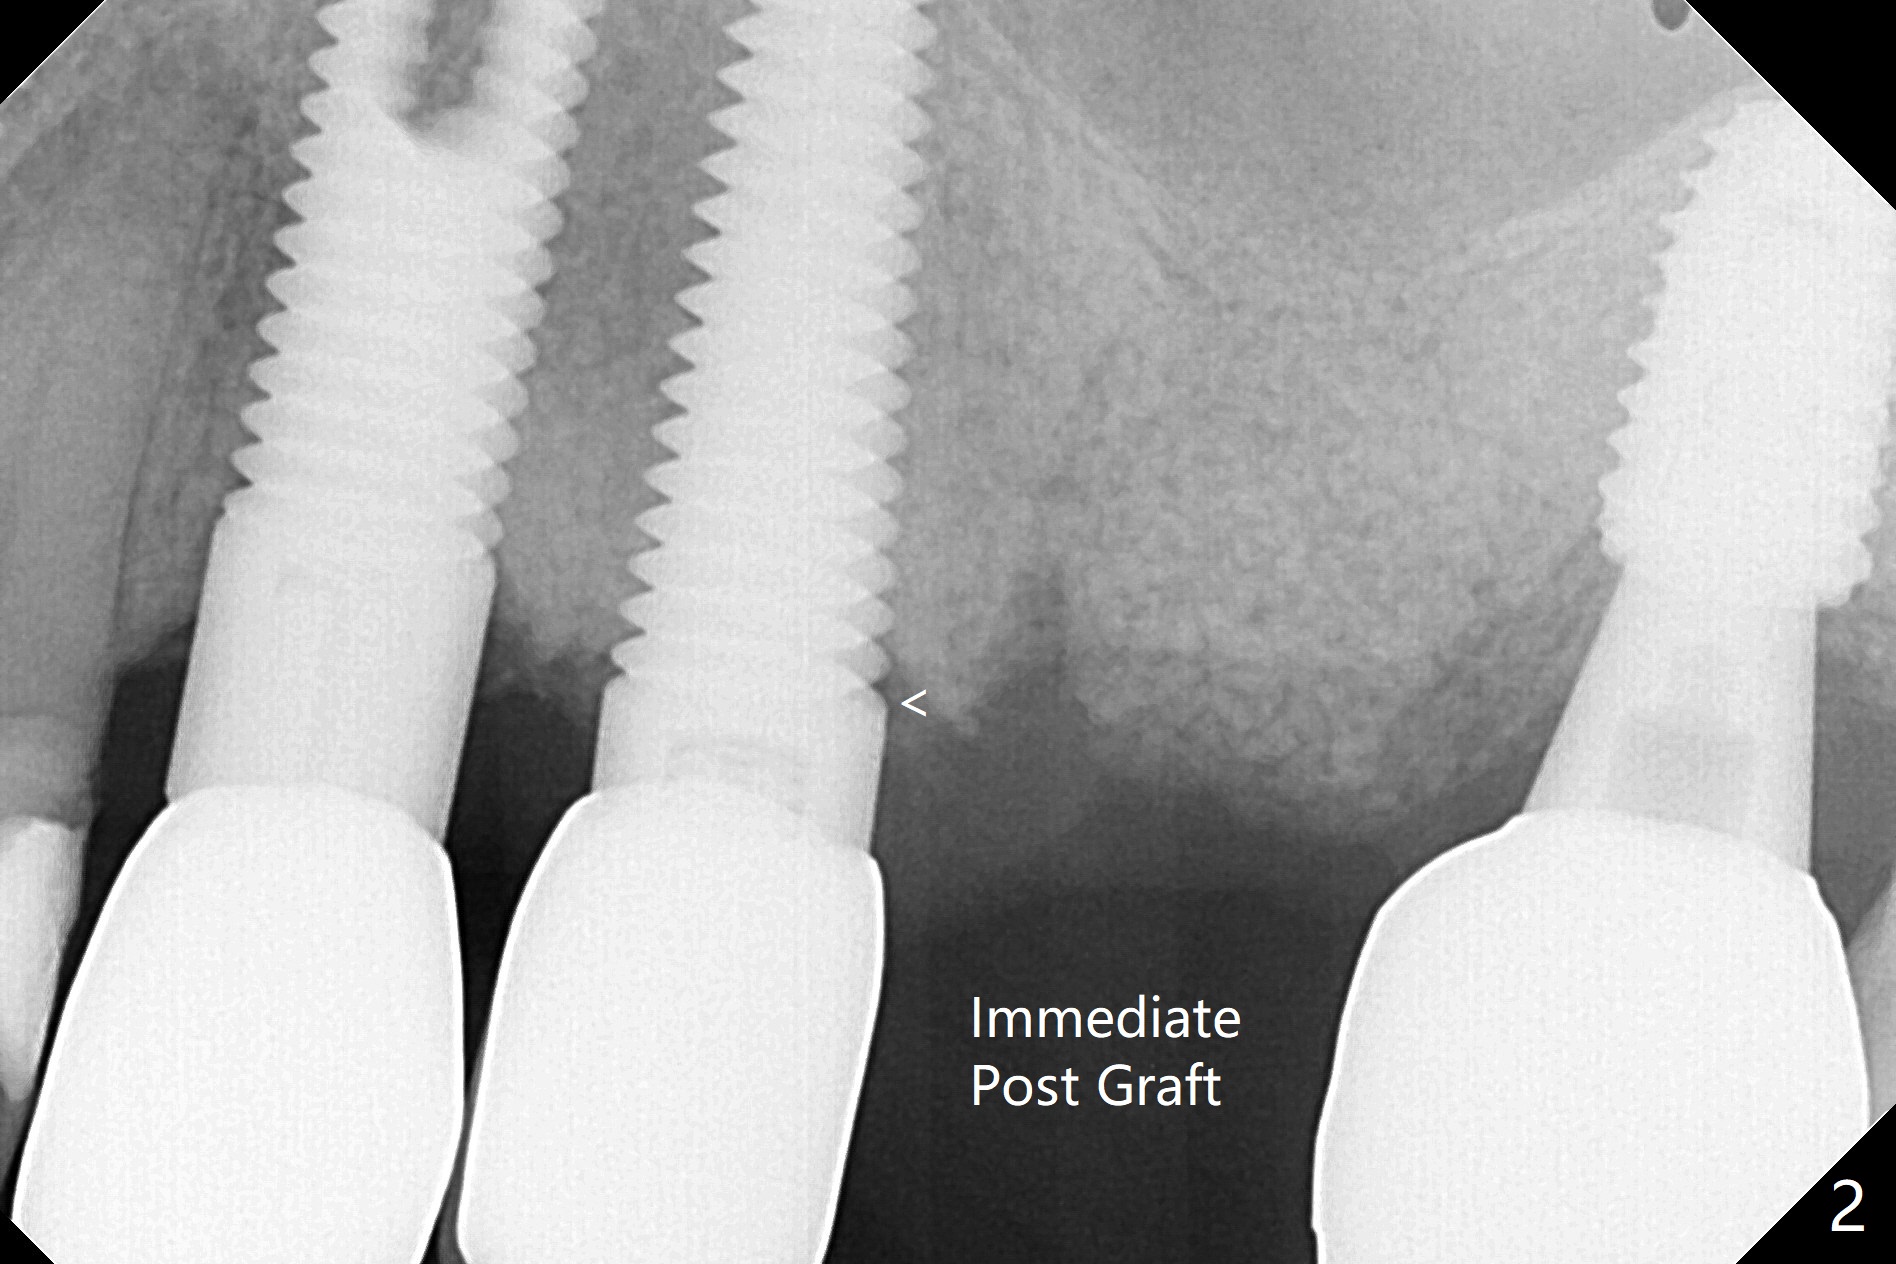

91岁男,刚诊断骨质疏松,准备服用骨质疏松药物Fosamax 70mg 每周一次。主诉左上植牙松动(图一),容易取出,颊侧骨板缺失,上颌窦底板好像完整,清创后,填入皮质骨粉(图二),GEM Cap,牙周胶水,牙周敷料。The buccal plate was present 1 year 4 months earlier (Fig.3). SM implants appear to have rapid bone loss associated with poor bone quality and bruxism.